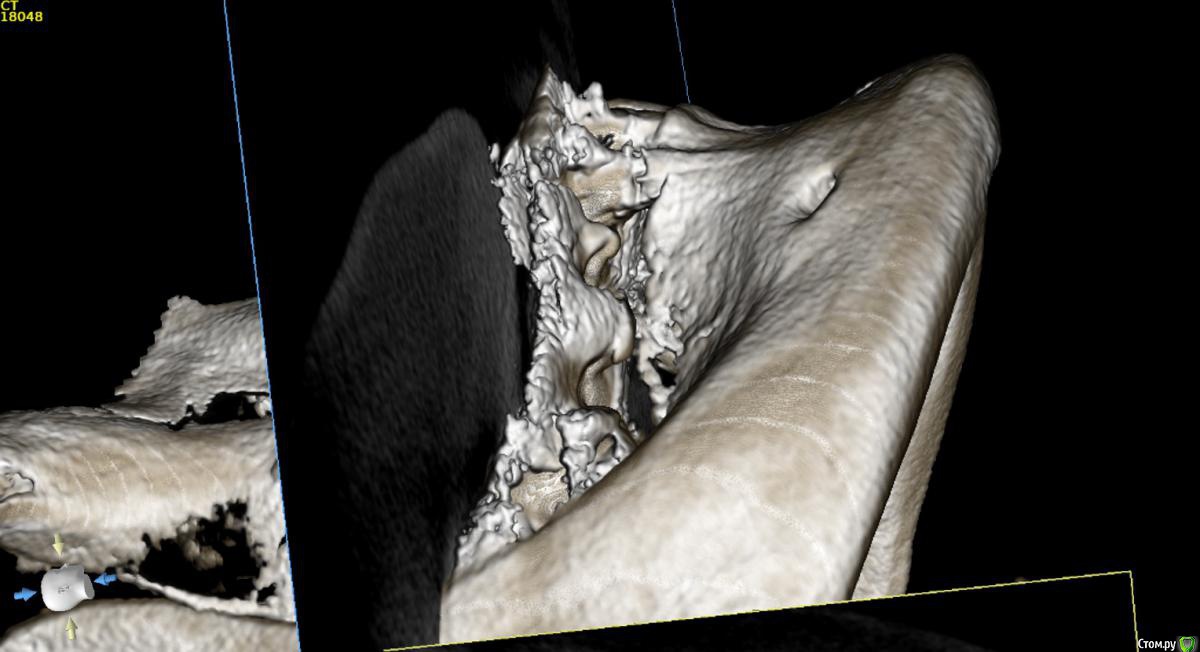

Nazim_NV86 Опубликовано 23 мая, 2018 Поделиться Опубликовано 23 мая, 2018 Посмотрите 3d rendering ( 3д визуализация). Что там видно с язычной стороны ? Ссылка на комментарий

Борис80 Опубликовано 23 мая, 2018 Автор Поделиться Опубликовано 23 мая, 2018 Посмотрите 3d rendering ( 3д визуализация). Что там видно с язычной стороны ?ничего не видно, смотрел Ссылка на комментарий

Борис80 Опубликовано 23 мая, 2018 Автор Поделиться Опубликовано 23 мая, 2018 какое то образование с четкими границами, достаточно большое, по структуре напоминает кость, но имеет четкий контур...в пределах челюсти, жалоб не предъявляет, с правой стороны(шрам на шее) была резекция подчелюстной слюнной железы, 3д моделировка снаружи: Ссылка на комментарий